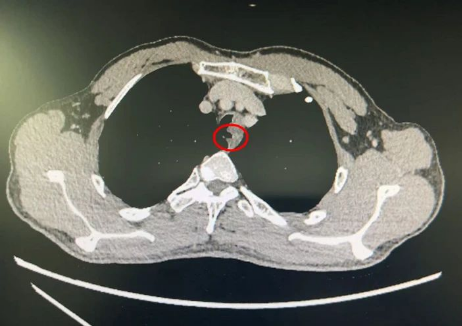

春节刚过,北京天坛医院胸外科主任魏博就在门诊看见了杜先生。由于反复咳嗽,杜先生到老家医院求医,发现气管腔内有肿物,并确诊为气管腺样囊性癌,“找了三家医院,都说做不了这个手术,后来在网上看到天坛医院胸外科有这方面的专家,就赶紧过来了”。“这种肿瘤发病率很低,由于气管的特殊结构,手术难度也比较大。”但杜先生的CT显示,他的气道已经被肿瘤堵塞了一大半,如果再发展下去,有可能危及到他的生命,魏博拍板,马上把杜先生收治入院。

第一关顺利通过,紧接着就是第二关:气管切除与重建。气管长度只有10-12厘米,切得范围太大,上下两段的气管可能会出现“对不上”的局面,而切得小了,则可能不能完全切除肿瘤。在气管镜的帮助下,手术团队精准地找到肿瘤的边缘,顺利切断肿瘤的下级。